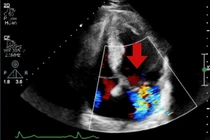

tim.jpg

Máy tạo nhịp tim không dây.